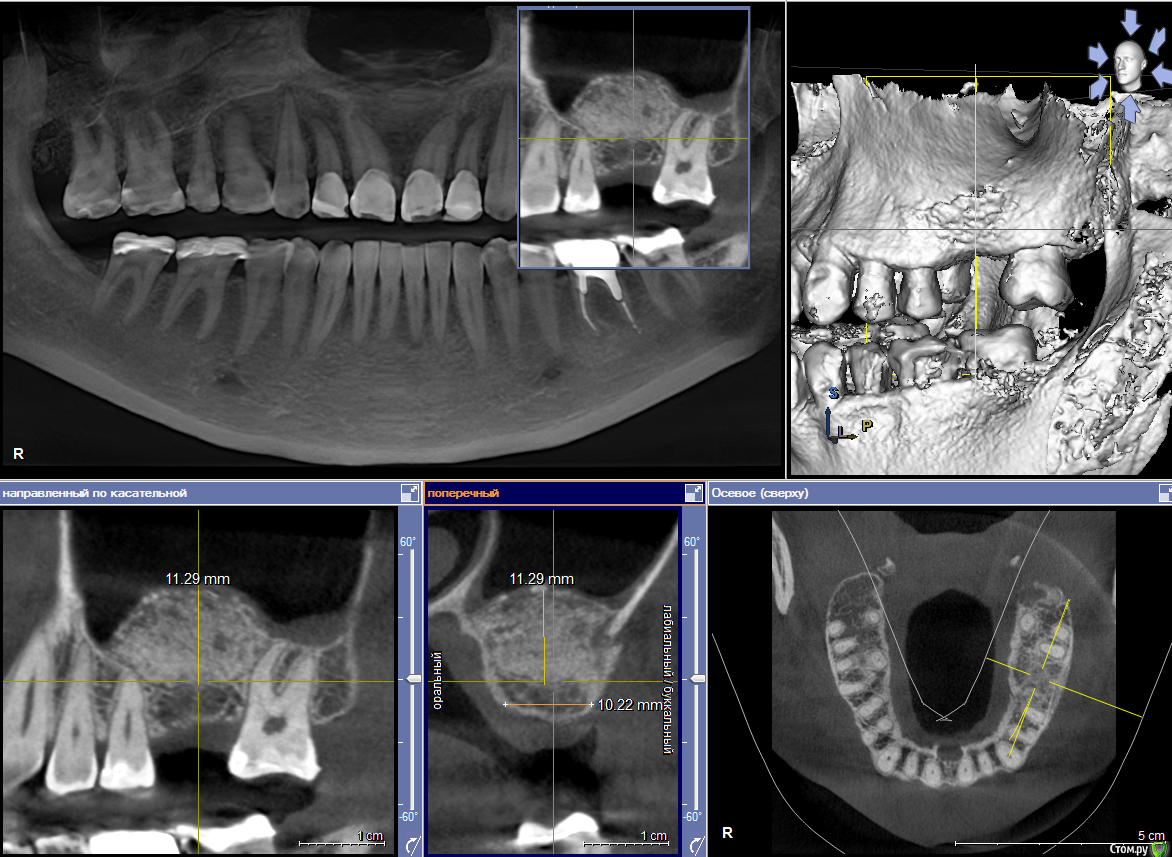

Dmitry DK Опубликовано 10 сентября, 2019 Поделиться Опубликовано 10 сентября, 2019 Фотопротокол к сожалению не полный, но ничего особенного и не проводилось. 1) Открытый синус, удален пломбировочный материал из пазухи, уложен 1 г Bio-oss 2) через 6 мес имплантация Straumann SP 4.1\10 Результат через год 9 Ссылка на комментарий